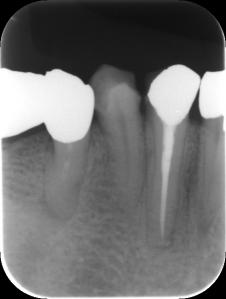

クラウンが壊れてしまっていたのか、しばらくそこに歯が入っていなかったという患者さんです。新しいクラウンが久々に入って喜んでおられますが、「ちょっと高い」とも感じておられます。

また、いまはまだ調整が完全には終わっていない段階のため、新しいクラウンは「仮止め用のセメントで付けてある」そうです。軽い違和感と、すぐにガッチリ留めてもらえなかったことが気になるのでしょうか。「先生がクラウンの製作を失敗したのではないか」と心配しておられます。

問題はむしろ、まだ慣れていない時期に、患者さんの一時的な違和感をもとに性急にクラウンを削ってガッチリ留めてしまうことです。歯科医はプロとして噛み合わせがきちっとできているかどうかを検査し、患者さん自身の使用感も大切にしながら総合的に判断していかねばなりません。本来なら削る必要のなかったクラウンを、削って止めてしまっては、最終的に噛み合わせが低くなり、せっかくのよい治療が台無しになってしまいます。

「患者さんのお口が新しいクラウンに慣れる様子を確認するまでは仮留めにしておき、次の調整で慣れの様子を見ながら最終調整して本格的に留めましょう」というやり方は、信頼のおける診療方針だと思います。